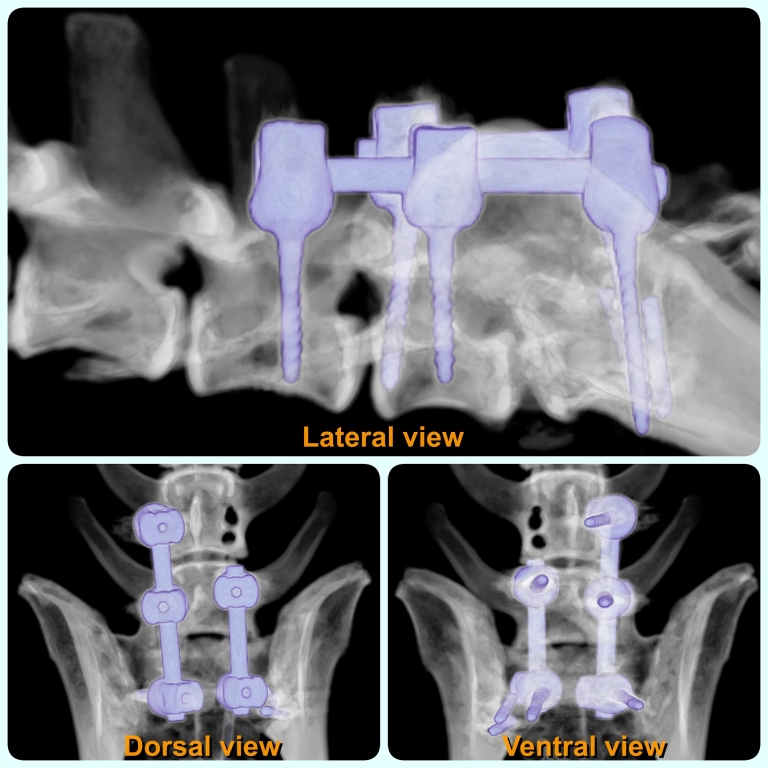

Three dimensional CT (3D CT) of the lumbosacral spine. Photo courtesy of Mr Menéndez (from the Imaging Team at Chestergates Veterinary Specialists)

As a last chance for Zedek, CVS’ Chestergates orthopaedic and neurology specialists Dr Dave Thomson and Dr Anna Tauro opted to use Neuromed’s new polyaxial screw system¹, which combines strength and stability. The Neuromed team was able to recommend the correct implant size based on CT scans, and arranged a fast shipment.

Zedek undergone successful surgery to relieve the compression: the previous implant was removed and the new implant was placed, and it remains stable at the follow-up check.